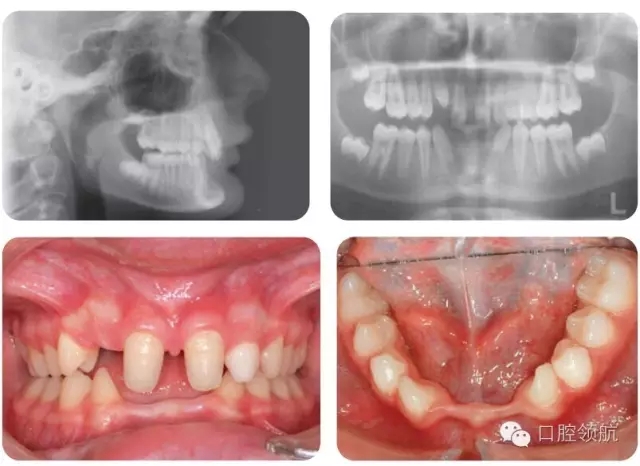

嚴(yán)重STHAG相關(guān)的主要臨床特征有哪些?(圖2.18)

圖2.18

● 嚴(yán)重的STHAG常與后縮側(cè)貌相關(guān),伴下前面高減小。垂直比例減小的病例常導(dǎo)致覆加深。

● 口內(nèi)特征根據(jù)只有1顆牙先天缺失的輕度病例或超過(guò)6顆牙缺失的重度病例而不同。嚴(yán)重病例通常有散在間隙和乳牙滯留。

● 常伴隨過(guò)小牙,可以是局部(釘狀側(cè)切牙)或廣泛的。

● 很多病例的滯留乳牙可以保留至成人階段。下沉的乳磨牙往往提示繼承恒牙缺失。

● 多顆牙缺失的病例,繼承恒牙缺失可導(dǎo)致頜骨發(fā)育不全,牙槽嵴狹窄。有時(shí)會(huì)出現(xiàn)側(cè)方開牙合。